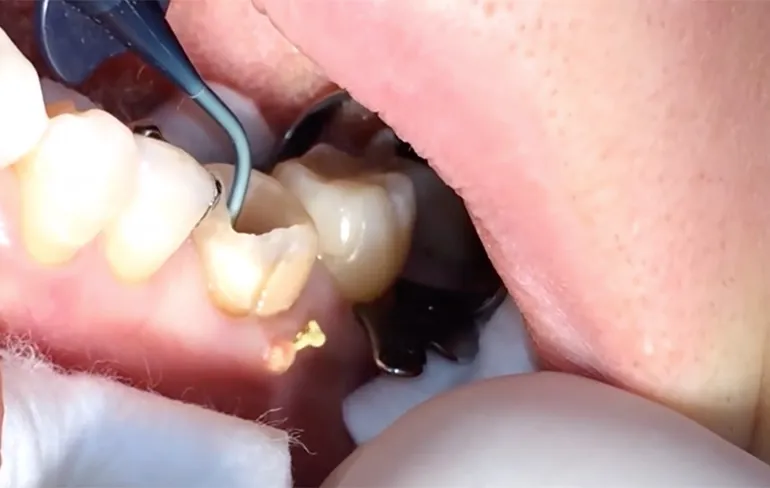

Er zijn een paar type video's waar je de gemiddelde internetter altijd voor wakker kunt maken. Dan zijn natuurlijke olijke kattenvideo's en video's waarbij iemand even een puist van 5 jaar en ter grootte van een tennisbal uitknijpt. Geen kattenvideo vandaag, maar wel een paar video's in de laatste categorie. De mensen die bang zijn voor een tandarts kunnen sowieso beter even deze video's overslaan, want anders slapen ze vannacht misschien heel slecht. We zien een tandarts aan het werk waarvan de patient last heeft van een rottende kies. En rottende kiezen en pus in het tandvlees zijn aan elkaar gelinkt en moet ook eerst verwijderd worden, voordat de tandarts alles weer mooi kan maken. Alleen dat is niet zo'n prettig gezicht! Is wel een keertje wat anders dan een neus vol mee-eters!